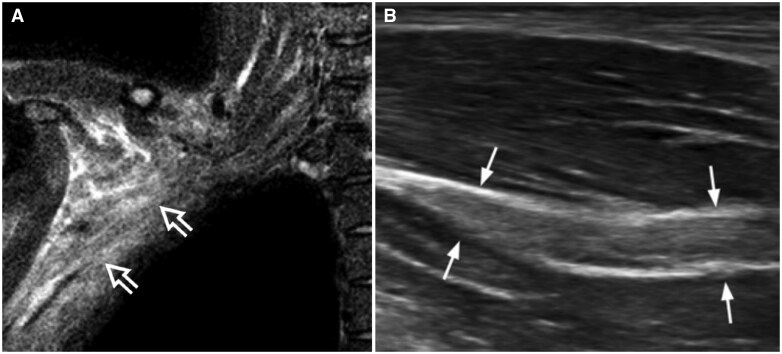

Ultrasound is as accurate as MRI in the detection of most brachial pathologies but tends to be underutilized in clinical practice compared to MRI. The main reason for this under-usage is a relative lack of knowledge regarding how to perform brachial plexus ultrasound and a lack of awareness of the ultrasound appearances of brachial pathologies. This review serves to re-address this imbalance by providing a practical overview on how to perform brachial plexus ultrasound as well as highlighting the ultrasound appearances of common pathologies likely to be encountered in everyday clinical practice.